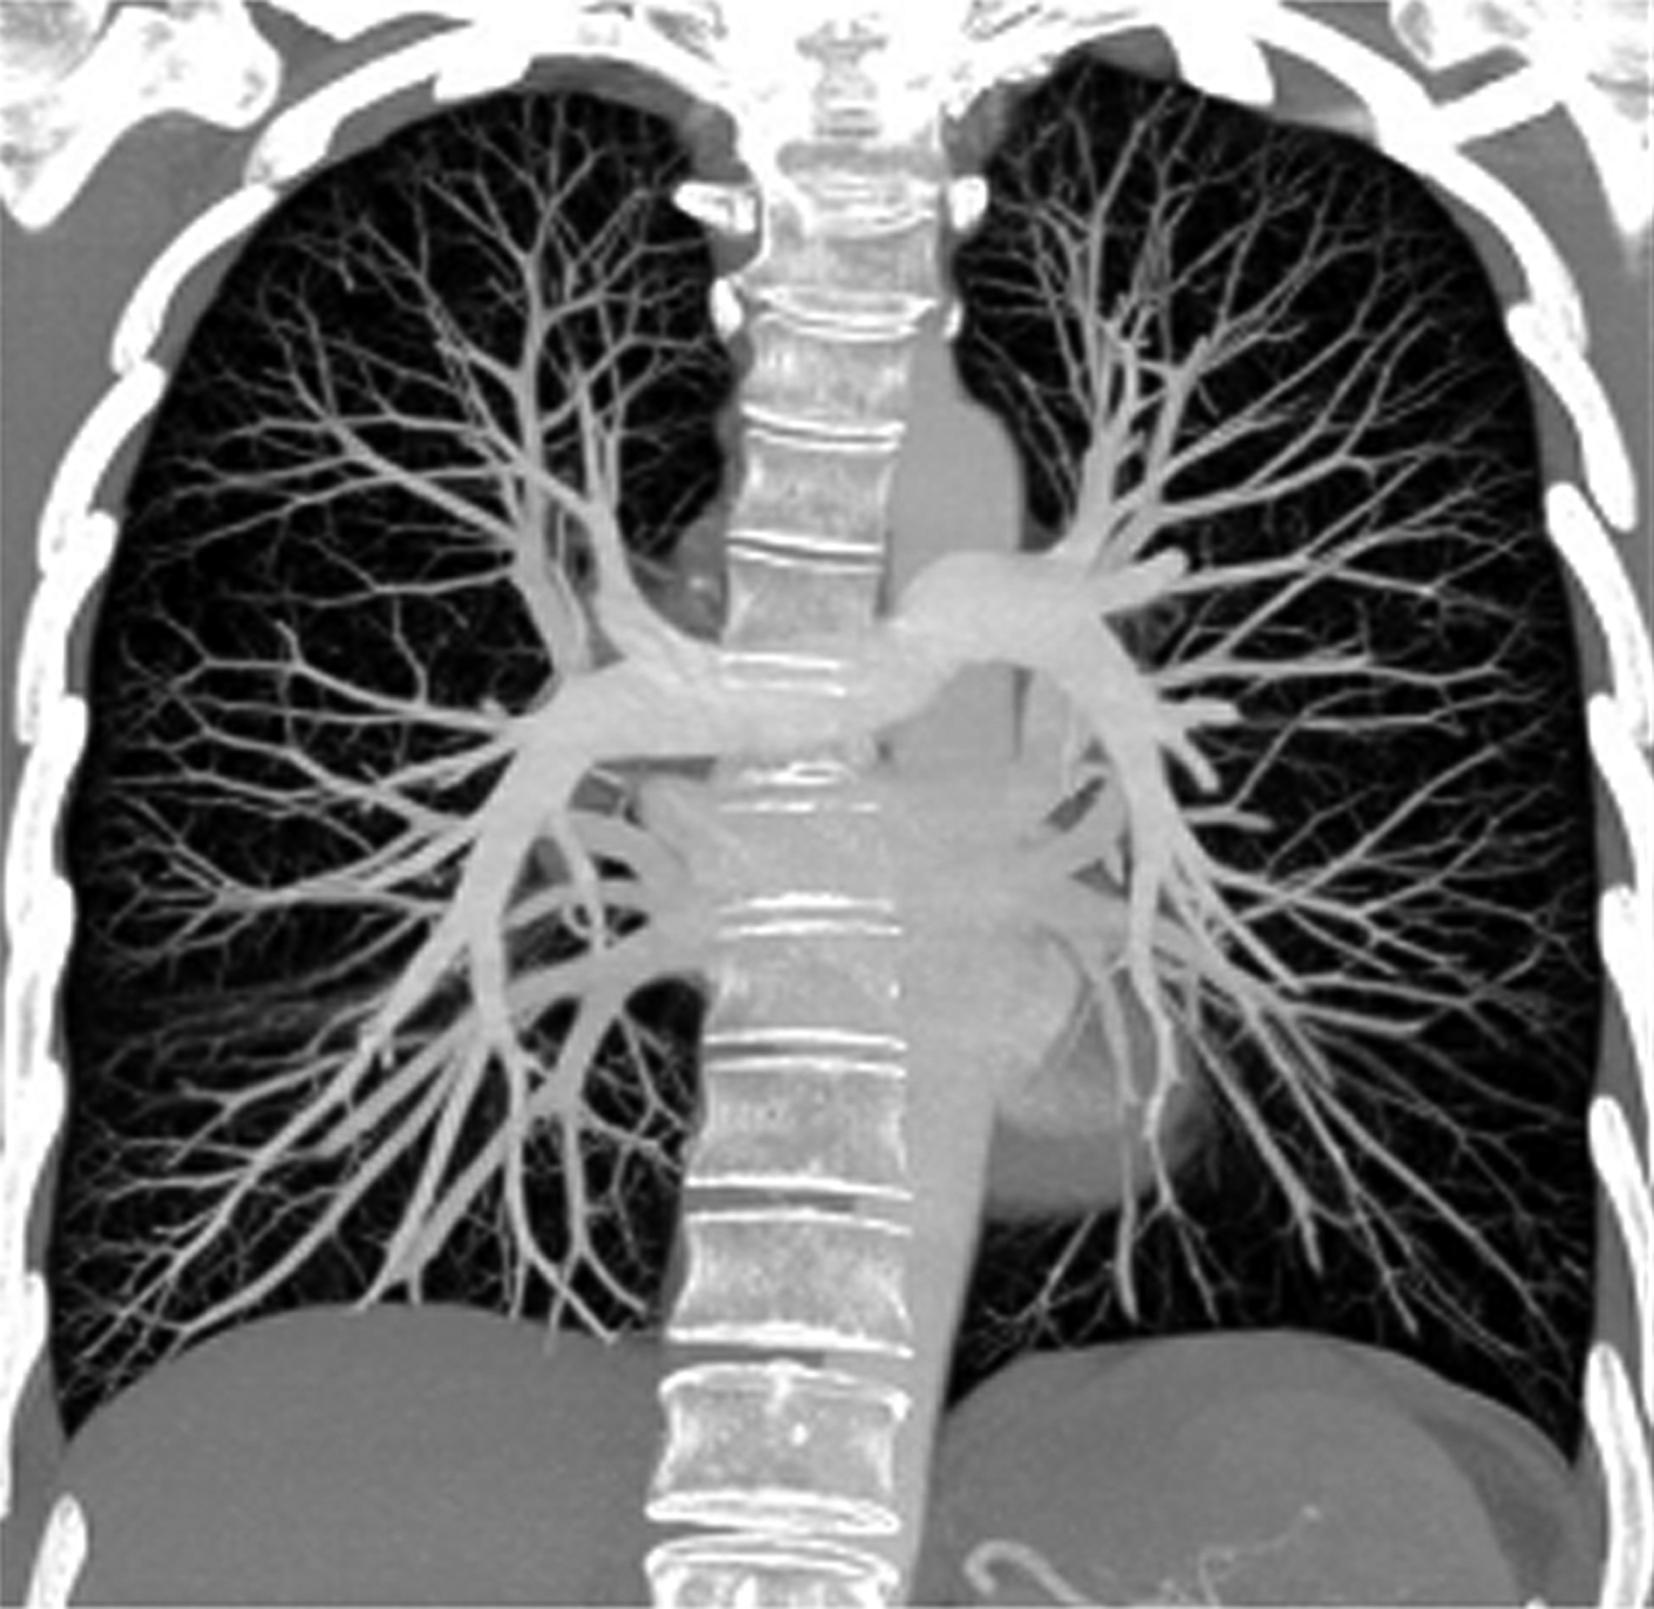

容积再现技术的优点是:①可以直观地反映物体的空间位置、结构和与其他器官的关系,是真正的三维立体重建;②容积再现技术保留了原始数据的全部信息,可以直接对图像进行分析处理,直接从立体图像上进行原始数据提取和测量,增强了交互性。对肺动脉及肺静脉疾患诊断有重要价值(图8-2-1)。

图8-2-1 肺动脉容积再现(VR)

正常肺动脉:A.冠状位;B.背面观;C.左前斜位;D.右前斜位